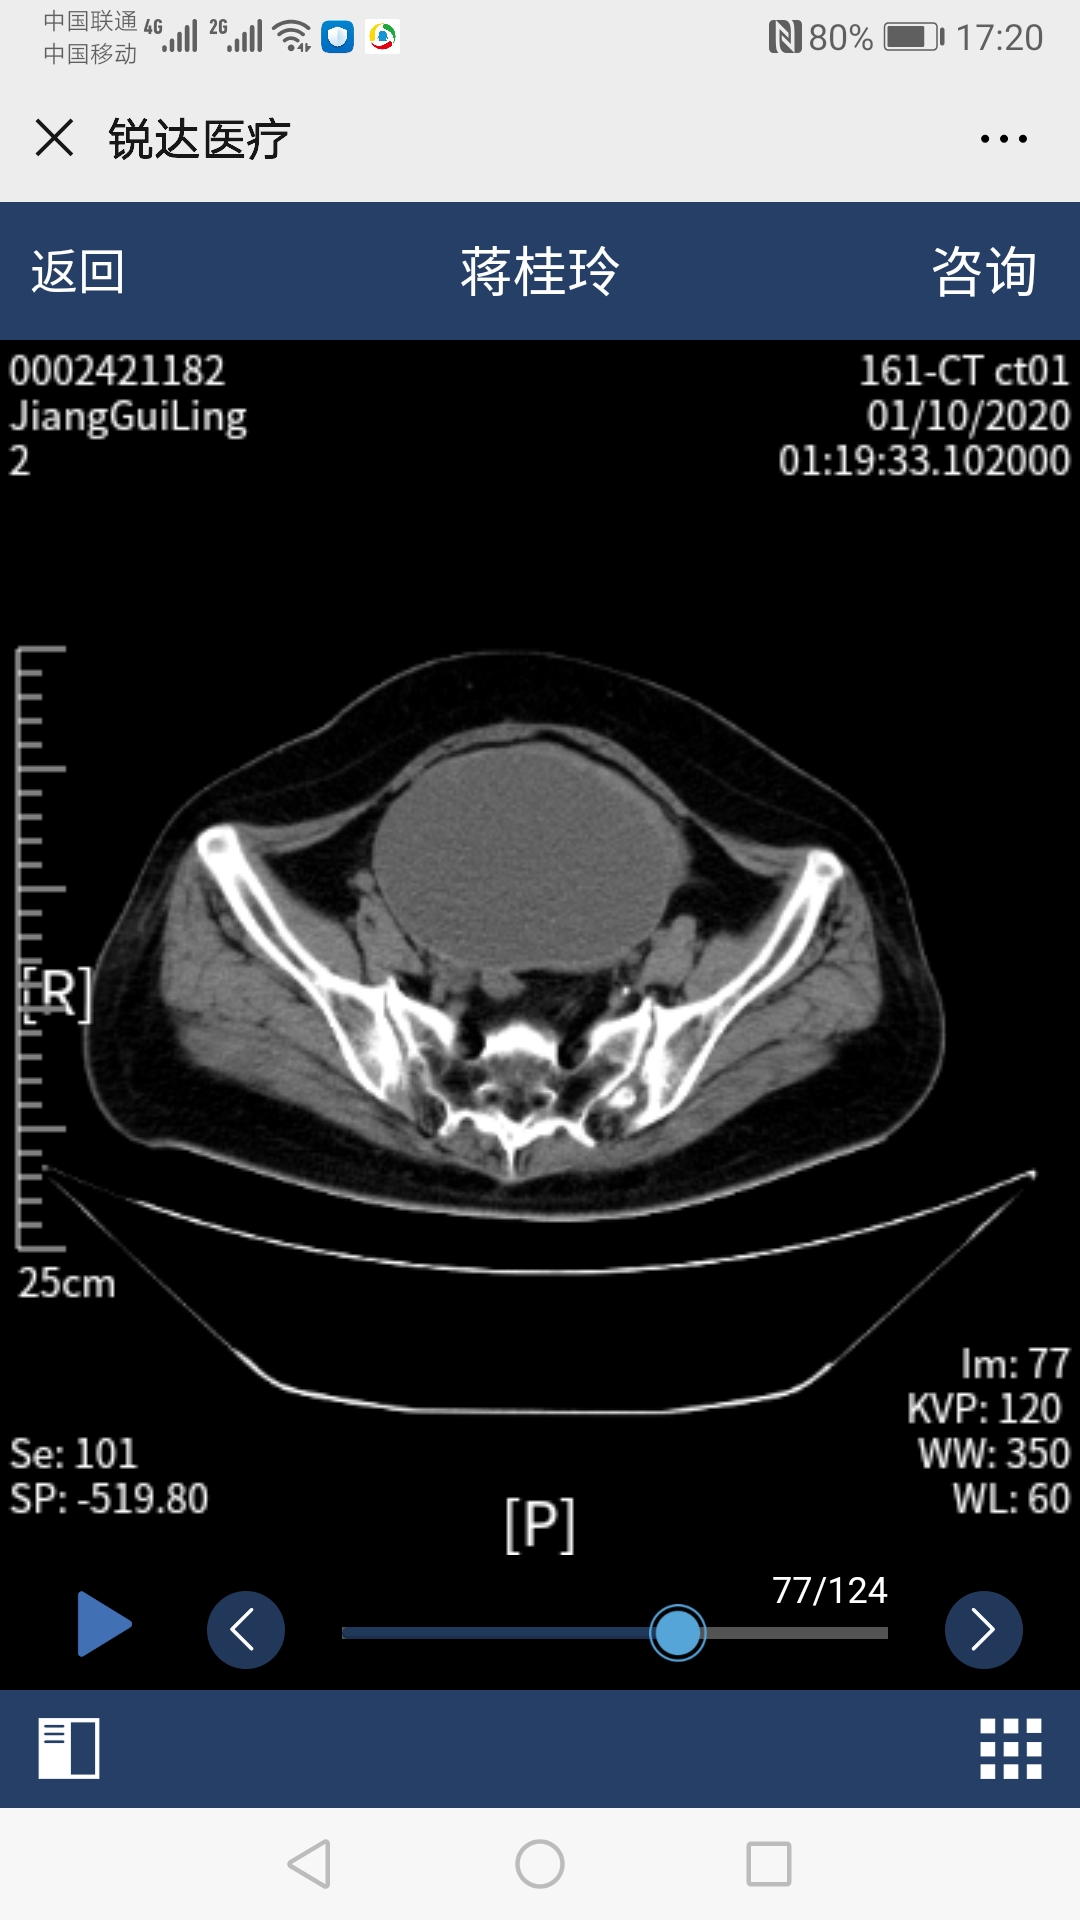

54岁的蒋阿姨最近常常觉得腹部胀痛,没有食欲,排便困难。肚子上出现一个包块,且越来越大。在当地医院就诊发现腹部有一个巨大的囊性肿物(12cm*8cm*12.6cm),但却同时检查出了患有先天性心脏病--房间隔缺损,并且已经出现了右心衰竭和明显肺动脉高压症状,加上既往冠心病、糖尿病、肾结石等多种疾病,医生在询问病史、完善检查之后说道:"你这手术风险太大,还是到别的医院试一试吧,我们这里不敢做"。蒋阿姨先后在省内多家大医院奔波求医,有的建议外科手术治疗腹部肿块,但因有房间隔缺损等多种疾病,风险较大;有的建议先做房间隔缺损手术,但术后需抗栓治疗6个月,期间不方便行腹部肿块手术,那就要继续忍受6个月的痛苦;总之,没有找到合适的方案。 正在蒋阿姨痛苦万分的时候,她听说哈医大四院心内科*巍杨**主任技术高超,医院整体实力雄厚,可能有更好的方案。蒋阿姨一家慕名来到了心内七病房,看着在病床上挣扎的蒋阿姨,杨主任急患者之所急,积极组织全院会诊,在院领导及医务科的协调下,邀请心内科、妇科、普外科、消化科、肿瘤科、心脏超声科、彩超室参与患者病情讨论,专家们建议患者先*房行**间隔缺损封堵术,再进行腹部囊肿穿刺术。手术于会诊后立即实行,*巍杨**主任、张明宇主任及心内科彩超室薛莉主任采用微创方法实施房间隔缺损封堵术,术后一周由彩超室董晓秋主任和刘瑞松医师为她做了腹部巨大囊性肿物穿刺引流术,3天共引流出1000毫升血性液体,后成功撤出引流管,蒋阿姨腹部胀痛等不良感觉消失。在心内七病房全体医护人员的悉心照料,蒋阿姨术后恢复良好,没有出现任何并发症及不良反应,顺利出院。